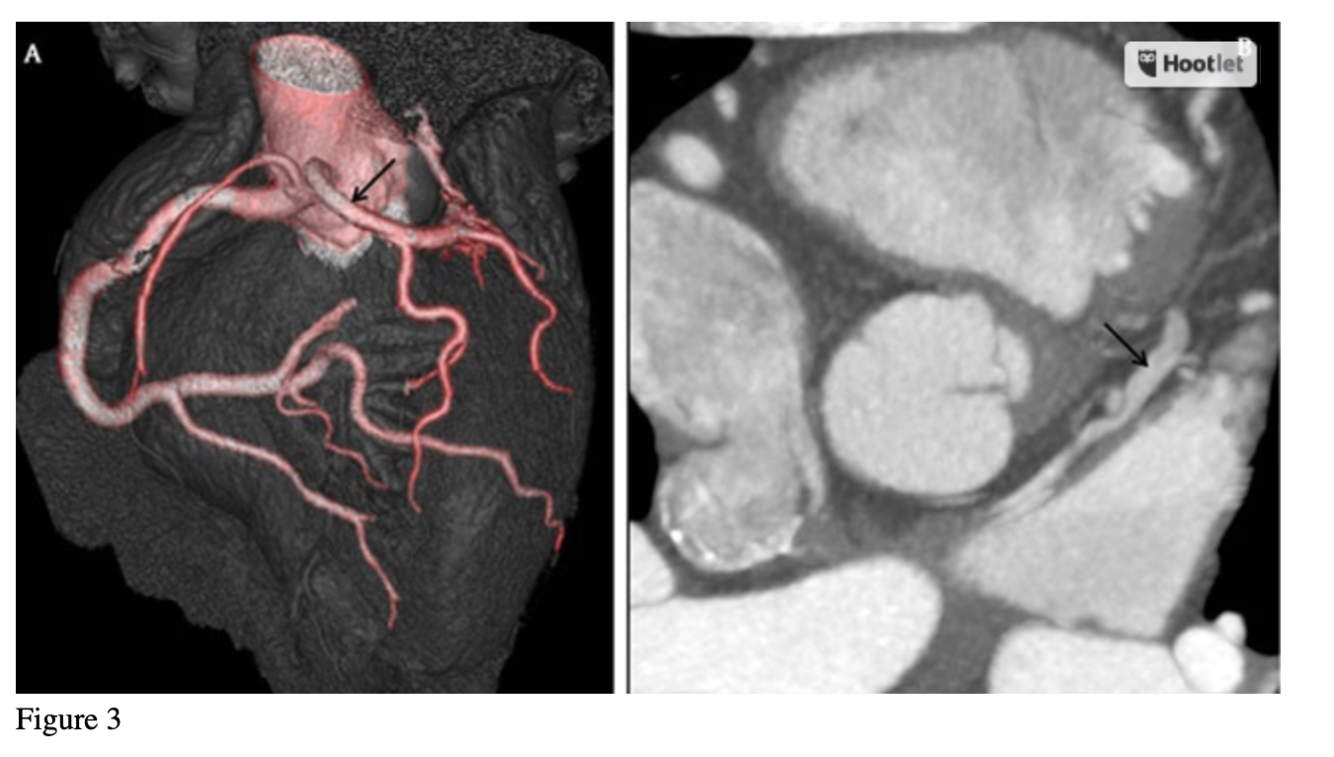

3a: Coronary CT angiography showing the origin of left main coronary artery (black arrow) from the right coronary sinus with prepulmonic course; 3b:Coronary CT angiography showing the anterior interventricular vein (black arrow) draining directly to the left atrium.